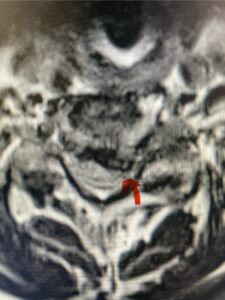

In this next case, this patient is a 47 year-old female who presents with intractable low back pain with severe pain, numbness, and weakness in the right lower extremity that had gotten progressively worse over a year. The patient had failed conservative management including physical therapy and epidurals. She was noted to have ⅘ weakness of plantar flexion. MRI demonstrated a large right L5-S1 disc herniation with severe compression of the descending right S1 nerve root (Fig 3). It was decided to perform a right L5-S1 hemilaminectomy for removal of the disc fragment and decompress the S1 nerve root. When you expose the disc, one must be certain to release any anterior adhesions to the nerve root in order to prevent a dural tear during retraction of the nerve root. It is also important to make sure during exposure and you finally encounter the dura after removing the ligamentum and fat, to make sure you are looking at the nerve root and not the main trunk of the thecal sac because if you don’t you can avulse or damage the nerve root if you retract the wrong structure.

Fig. 3a: Sagittal and axial T2-weighted lumbar MRI images demonstrating large right L5-S1 disc herniation (red arrows)

Fig. 3b